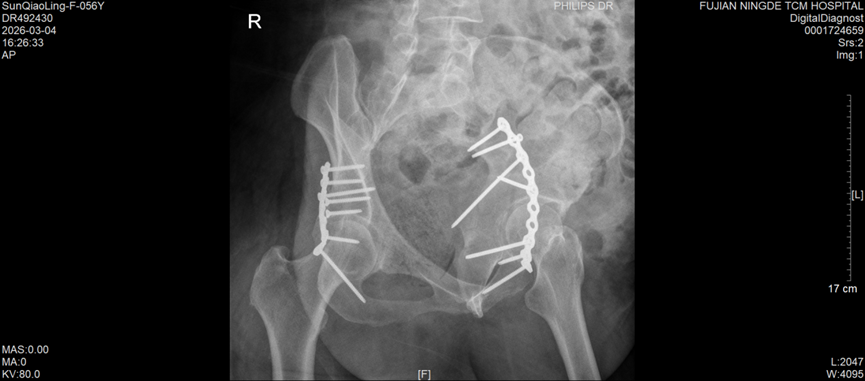

今年57岁的孙女士,因车祸外伤被紧急送往宁德市中医院创伤骨科就诊,经检查确诊为右侧髋臼后壁骨折伴股骨头后脱位,左侧髋臼T形骨折且累及四边体。据了解,髋臼骨折多由高能量损伤引发,其解剖结构复杂,毗邻重要血管神经,复位精度要求高、手术风险大,一直是创伤骨科领域的高难度手术,而双侧髋臼骨折更是该领域中极具挑战性的病例,不仅创伤重、术中出血风险高,诊疗难度也大幅提升。更为棘手的是,孙女士还合并有严重糖尿病及Ⅰ型呼吸衰竭,这无疑进一步增加了病情的复杂性和诊疗的艰巨性。

手术过程中,创伤骨科团队凭借扎实的解剖知识和娴熟的手术操作技巧,小心翼翼地进行组织精细分离,精准完成骨折复位,随后顺利实施牢靠的内固定操作,全程注重保护周围神经血管,严格控制术中出血和组织损伤。得益于周密的术前方案和精准的术中操作,此次手术总出血量控制在传统单侧髋臼骨折手术的常规水平,手术进展顺利。

术后,医护团队针对孙女士的具体情况,实施个体化镇痛、抗凝治疗,并引入快速康复(ERAS)管理理念,全程密切监测患者病情变化,及时调整康复方案。目前,孙女士恢复情况良好,未出现任何术后并发症,髋关节功能正稳步恢复,已进入有序的康复阶段。